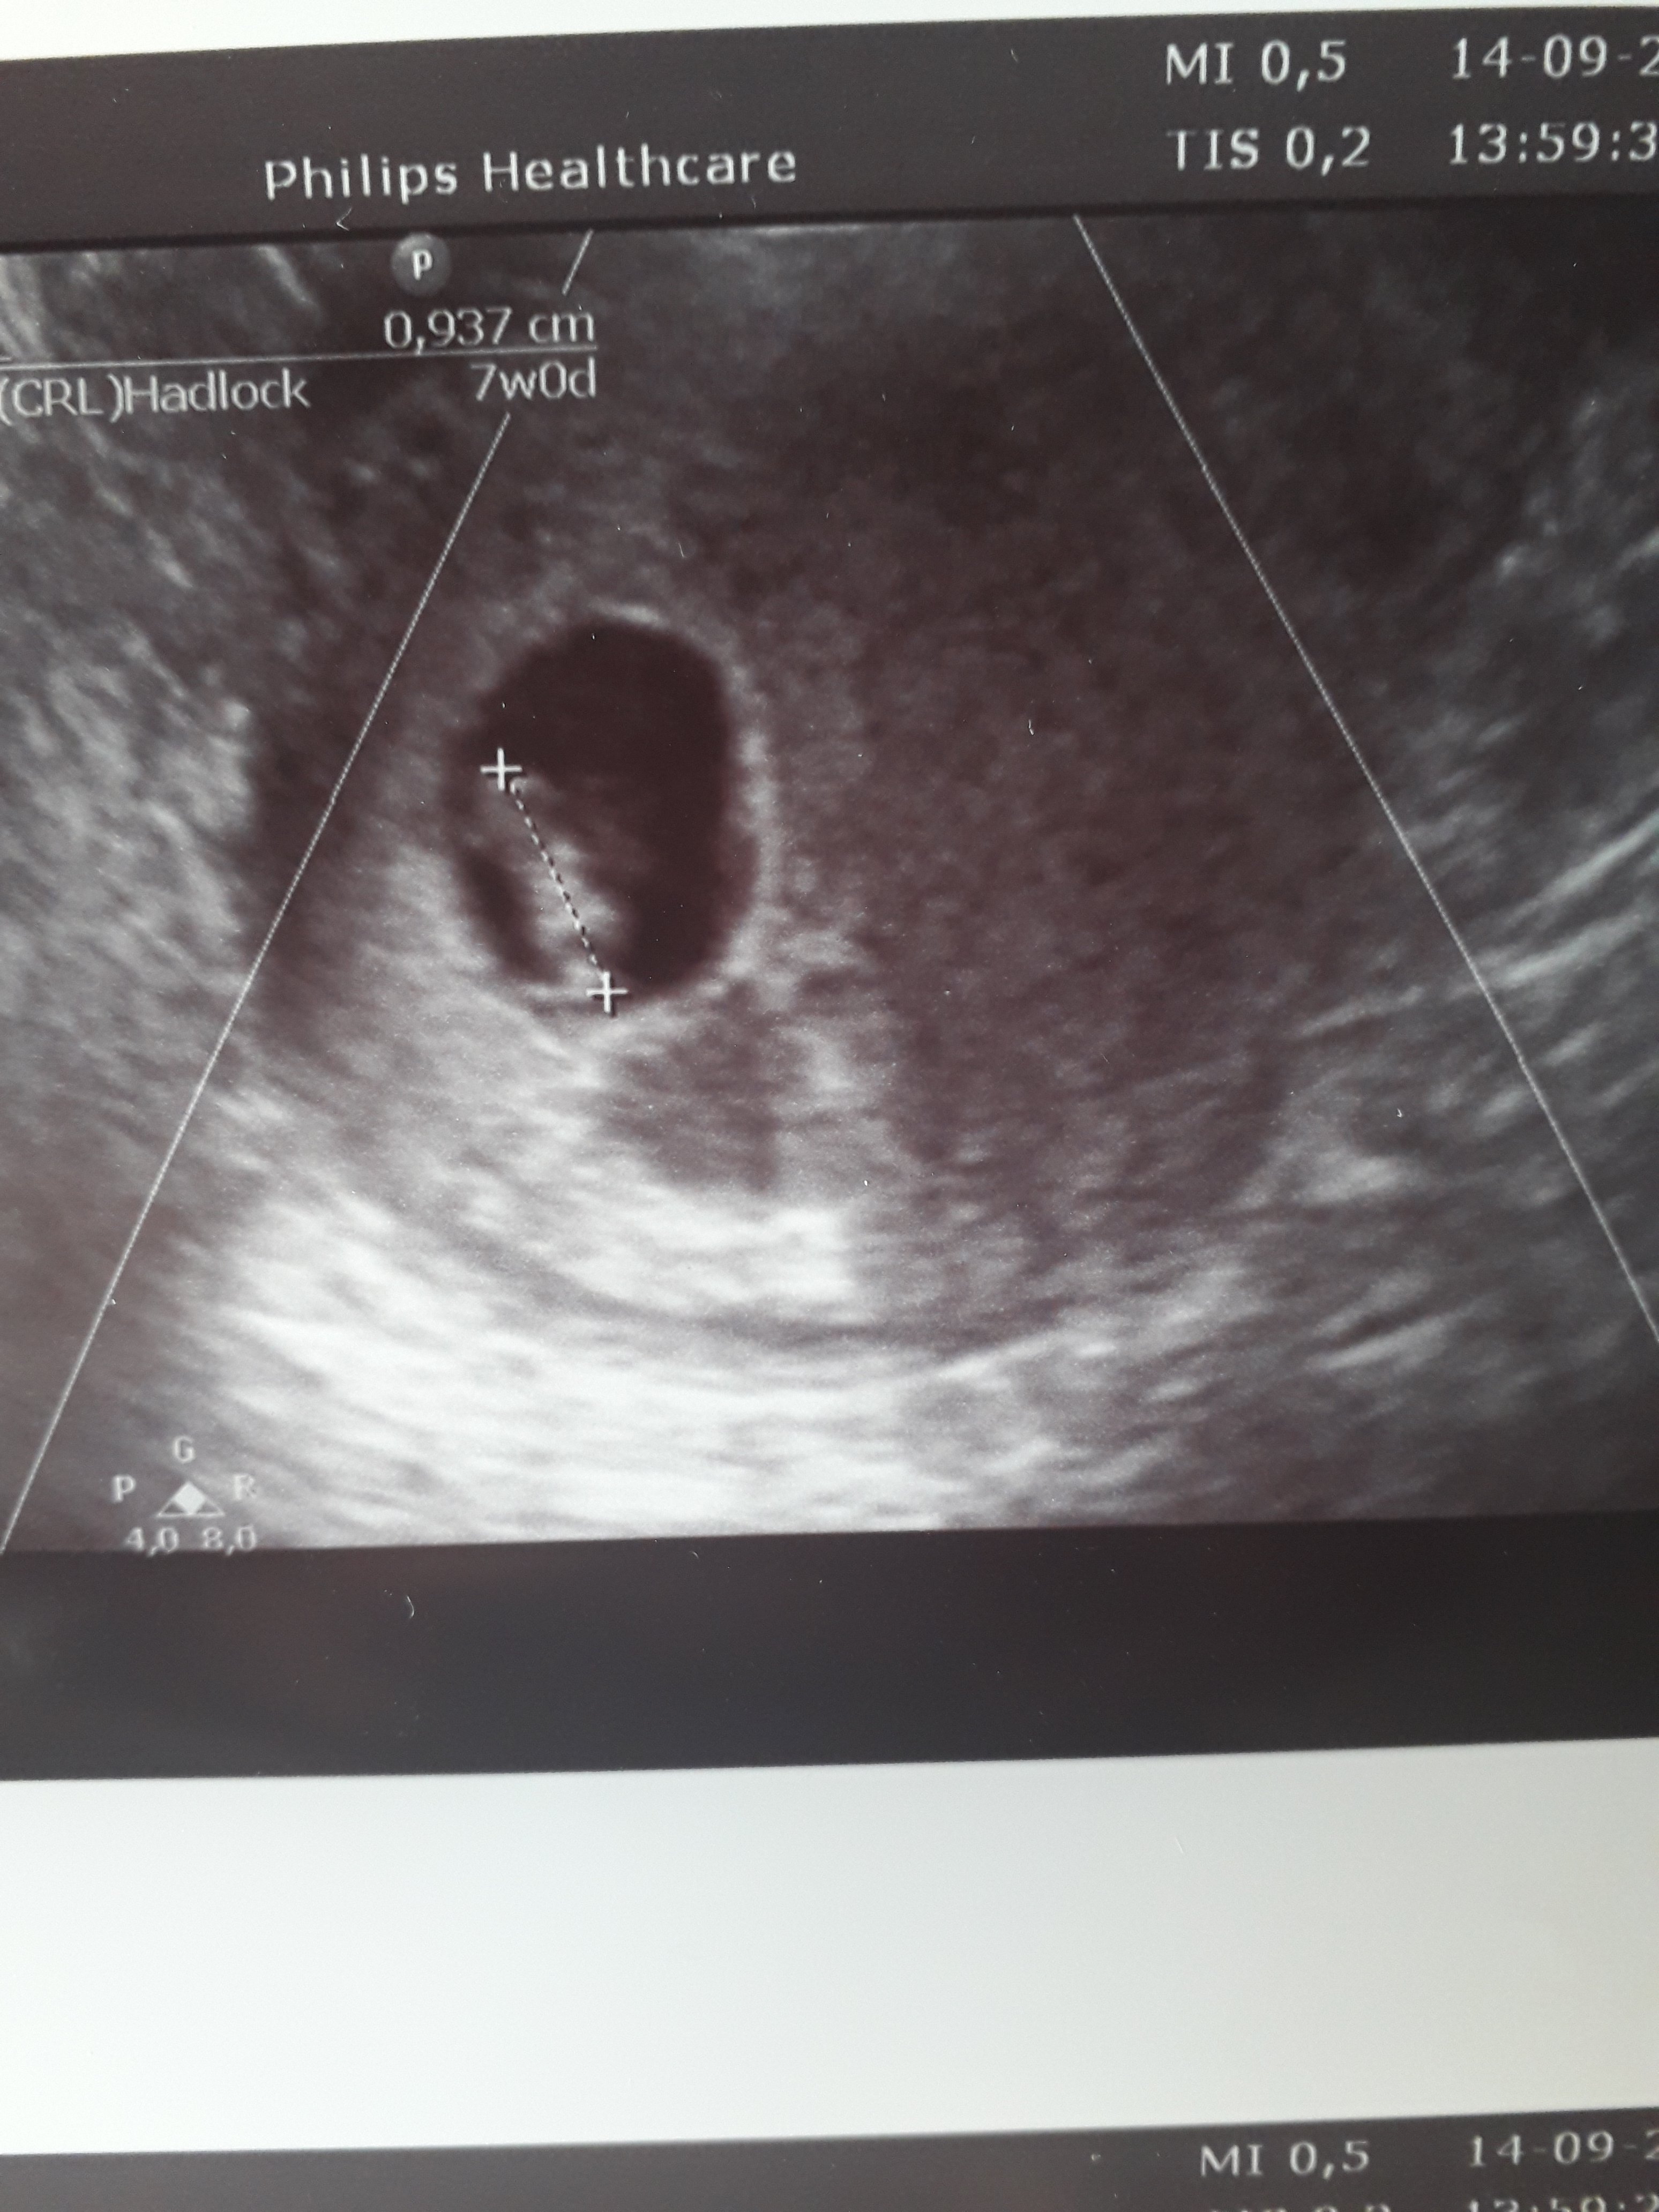

Ja już też po wizycie, zarodek jest, serduszko jest, ale i tak wyszłam podłamana, bo jest i krwiak, pomimo Acardu i zastrzyków... Nie rozumiem skąd to się bierze... Dopiero teraz jak trochę ochłonęłam to zaczęłam się cieszyć, że jest serduszko, i że póki co maleństwo dobrze się rozwija 😊 Jednak pani doktor powiedziała, że nie wiadomo jeszcze w którą stronę to pójdzie. Mam odpoczywać, brać luteinę 2×2 i zjawić się u niej za tydzień we wtorek.